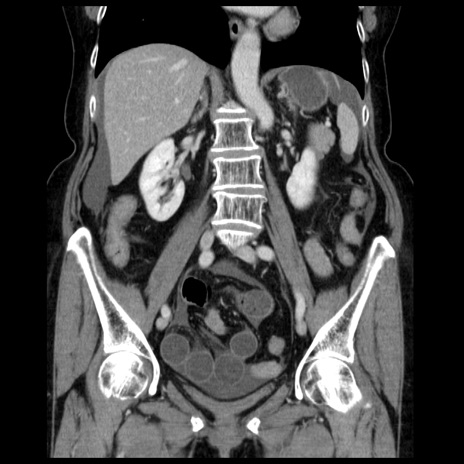

症例13(冠状断像)

【症例】70歳代女性

【主訴】腹痛、嘔吐

【現病歴】15時間程前(昨晩)より腹痛あり。今朝になっても症状の改善なく、嘔吐あり。腹痛も増悪あり、救急外来受診。

【既往歴】子宮癌全摘術後

【身体所見】意識清明、BP 121/72mmHg、P 74bpm、SpO2 100%(RA)、腹部:平坦・軟、腸雑音ほぼ聴取せず。下腹部・心窩部・臍左上に圧痛あり。反跳痛なし。

【データ】WBC 10600、CRP 0.15